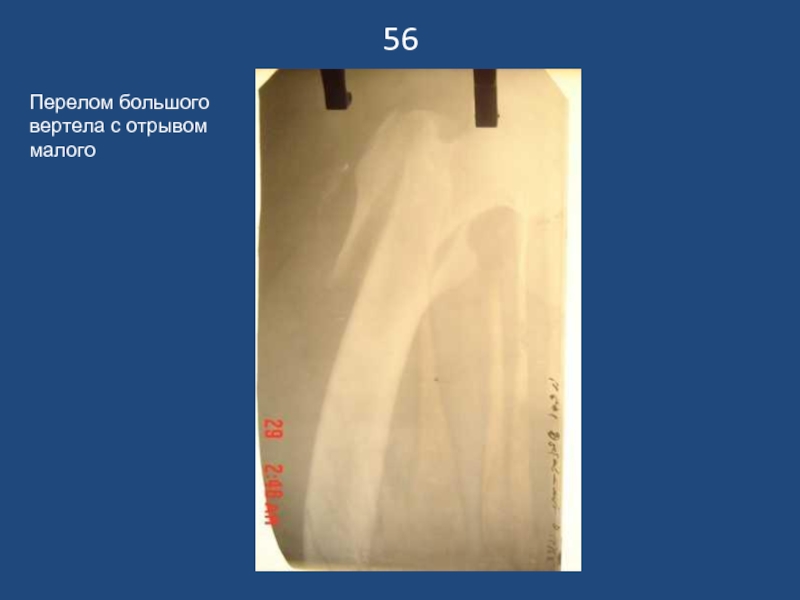

Слайд 5756

Перелом большого вертела с отрывом малого